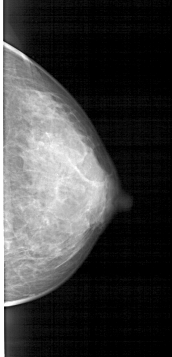

A_1446_1.RIGHT_MLO

RIGHT_CC LINES 4636 PIXELS_PER_LINE 2236 BITS_PER_PIXEL 12 RESOLUTION 43.5 NON_OVERLAY